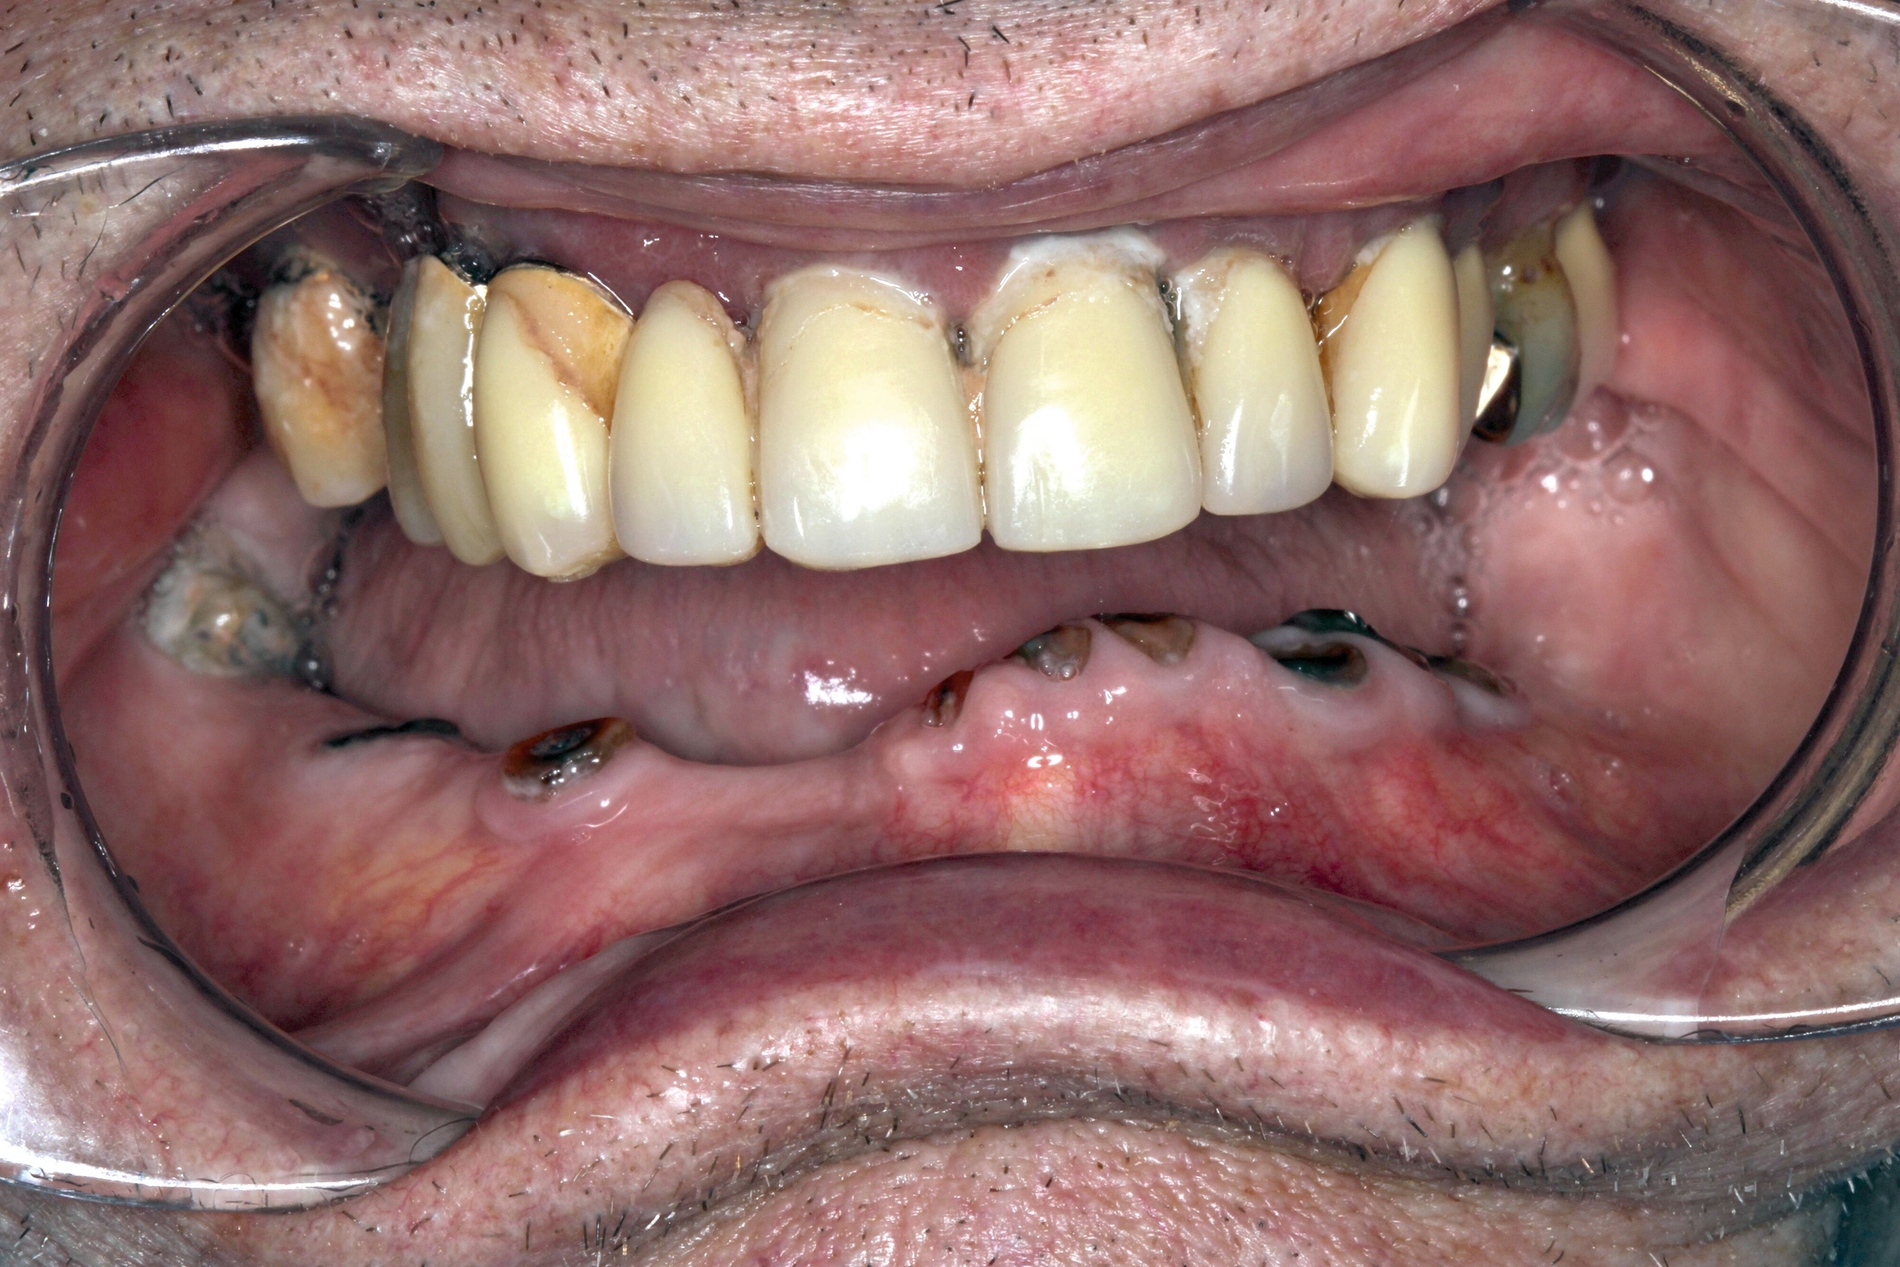

Die Herausforderungen der zahnmedizinischen Betreuung im höheren Lebensalter liegen außerhalb der Mundhöhle und haben nur indirekt etwas mit dem Alter zu tun. Im höheren Lebensalter steigt die Gefahr für Erkrankungen und Funktionseinschränkungen wie Gebrechlichkeit (Frailty), Demenz und Depressionen und/oder internistische sowie muskuloskelettale Erkrankungen. Diese Erkrankungen und Funktionseinschränkungen führen zu einer reduzierten Mundhygienefähigkeit der betroffenen Person. In der Folge kommt es besonders im vorgeschädigten Gebiss zu einer schnellen Progression kariöser oder parodontaler Erkrankungen. In Kombination mit organischen Funktionseinschränkungen wie zum Beispiel einer medikamenteninduzierten Xerostomie führt die Summation der Noxen – auch bei Personen, die ihre Mundgesundheit bis dato aufrechterhalten haben – zu oralen Komplikationen wie Zahnverlust und Entzündungen (Abbildung 1).